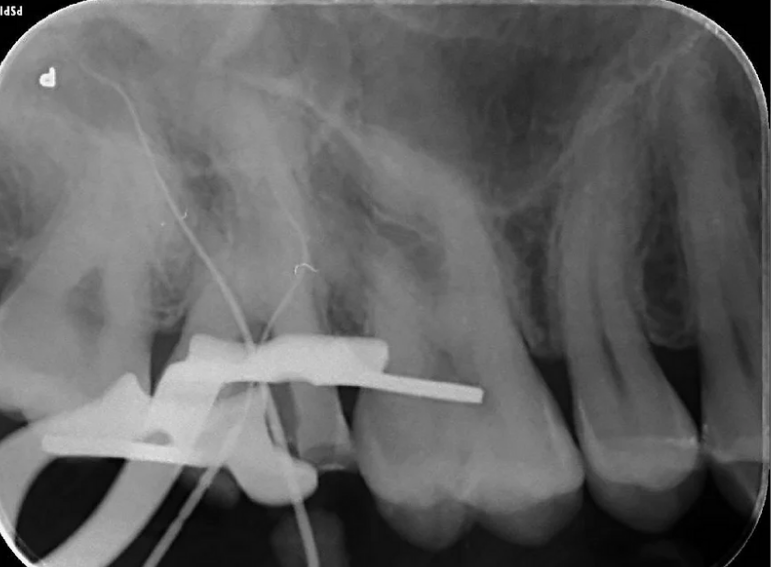

Surgical management of external cervical resorption.